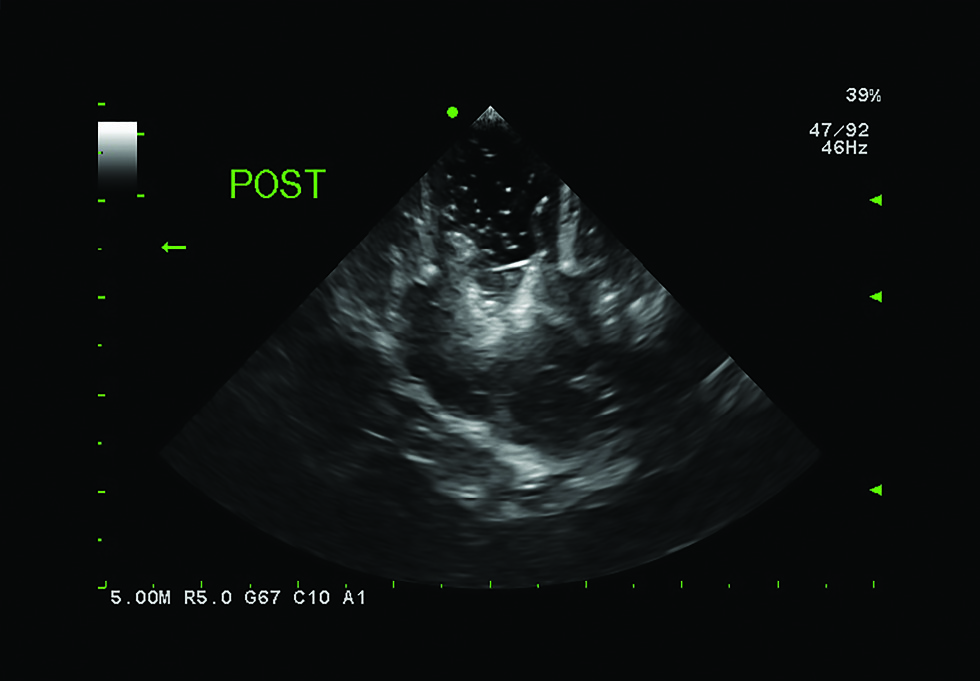

Subcortical Procedure using S12BP4

Subcortical guidance with precise access, improved efficiency and better results.